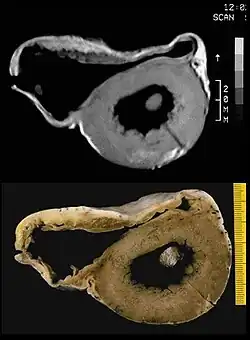

MRT-Aufnahme und pathologisches Präparat einer ACM

Die arrhythmogene Kardiomyopathie (ACM), früher auch arrhythmogene rechtsventrikuläre Kardiomyopathie (ARVCM) oder Dysplasie (ARVD) genannt, ist eine genetisch bedingte Erkrankung.[3] Ursächlich sind Mutationen von Proteinen des Desmosomen-Komplexes.[4] Desmosomen sind für den Zellkontakt der Zellen wichtig.

In der ursprünglichen rein "rechtsventrikulären" Form wurde beschrieben, dass mit dem Fortschreiten der Erkrankung immer mehr Muskulatur der rechten Herzkammer durch Fettgewebe ersetzt wird, wodurch sich die rechte Herzkammer vergrößert. Selten finden sich Einschränkungen in der Pumpfunktion des Herzens. Häufiger ist der bei körperlicher Belastung, wie beispielsweise Leistungssport, ausgelöste plötzliche Herztod (PHT) oder „Beinahe“-PHT, insbesondere bei jungen Menschen. Die Diagnose kann mittels Echokardiografie, MRT, EKG und McKenna-Score gestellt werden. Zur Behandlung kann ein Kardioverter-Defibrillator implantiert werden. Sportliche Belastungen sollten vermieden werden. Eine Herztransplantation ist in vielen fortgeschrittenen Fällen die Ultima Ratio.